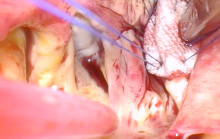

The operation was performed through a 5 cm right anterior thoracotomy under videoscopic guidance. Central aortic and peripheral venous cannulation was performed under TEE guidance. Cardiopulmonary bypass (CPB) was initiated, and the patient was cooled down to 28°C. A transverse aortotomy was made in the ascending aorta, with antegrade cardioplegia being delivered directly via the right and left coronary ostia. The aorto-atrial fistula was readily identified. Patch closure of the fistula on the aortic side was performed using a Hemashield graft with running 5-0 polypropylene suture. The aortotomy was closed, the left ventricle and ascending aorta were deaired, and the aortic cross-clamp was removed. The atrial side of the defect was then addressed. The superior and inferior vena cavae were snared, and a right atriotomy was made. The windsock was easily identified and was suture ligated with 3-0 polypropylene. The right atriotomy was closed and CPB was discontinued.